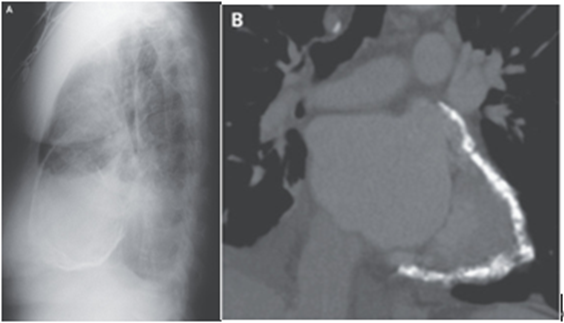

胸部X-pでは心膜の周囲の石灰化、胸水貯留、肺間質浮腫が示唆され、胸部CTでは広範な心膜石灰化が明らかになった。